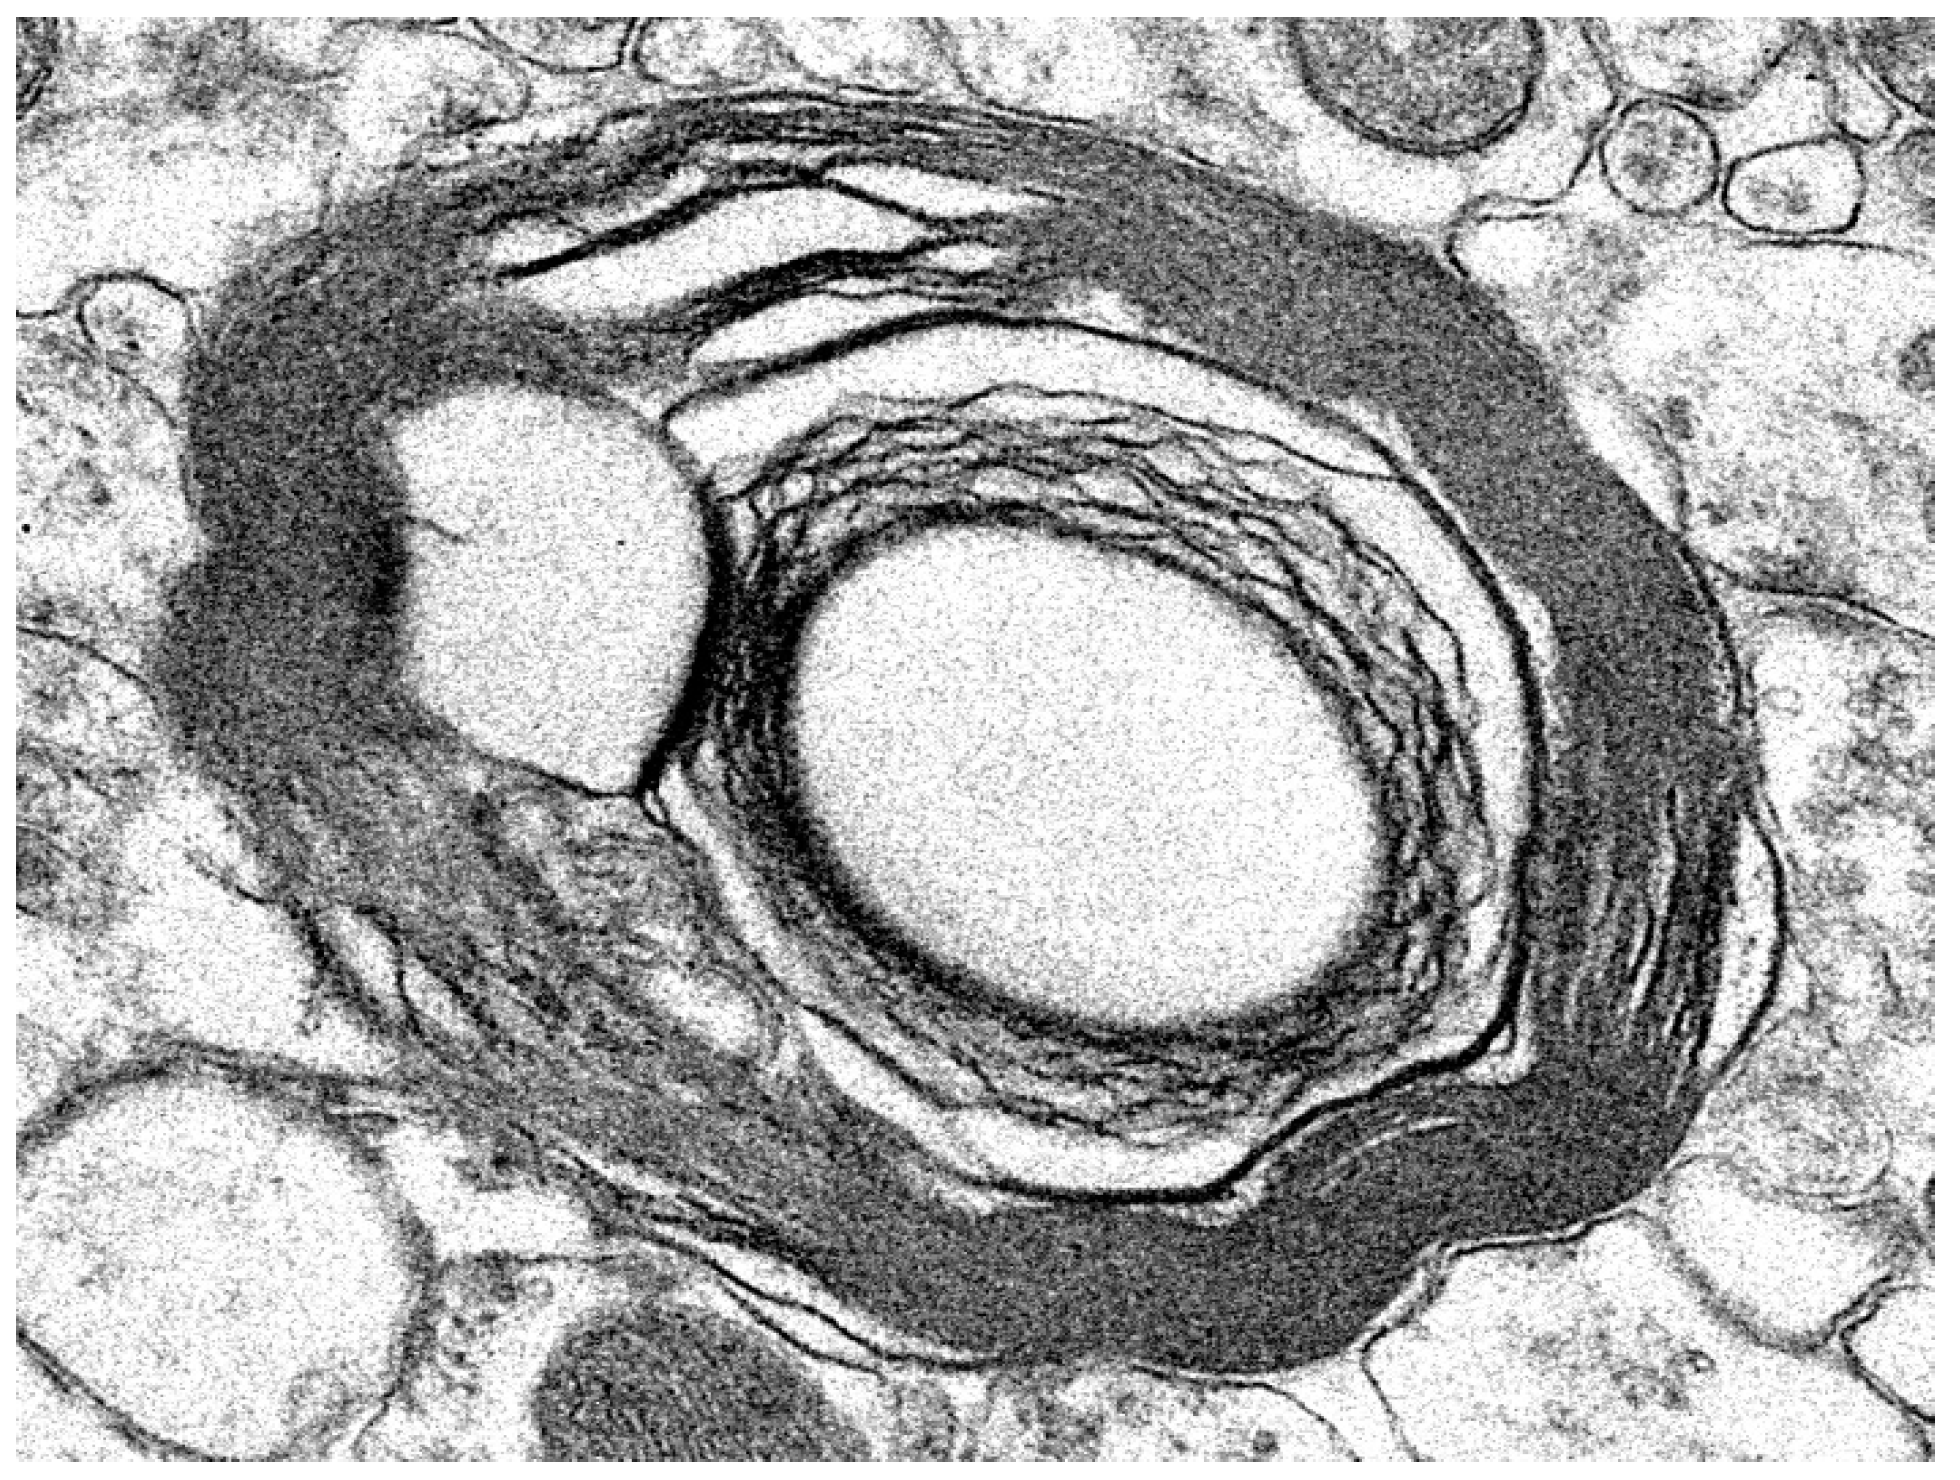

3.1. Disease Pathology